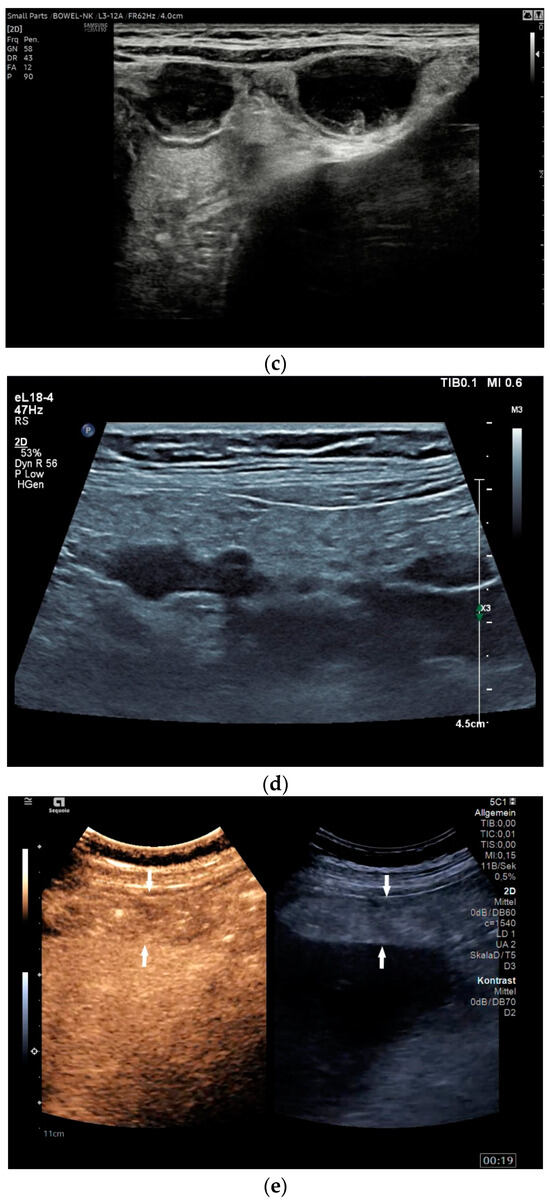

Spleen involvement usually only occurs in disseminated disease. The manifestations are splenomegaly, hypoechoic micronodular (miliary), or macronodular lesions [8,74], as well as splenic abscesses [75] [Figure 4a–d]. In a group of patients with tuberculosis and mostly advanced HIV infection, 37% had splenic lesions [5]. In 33%, splenic lesions were associated with lymphadenopathy, and 16% each had splenic lesions and ascites or splenic lesions, ascites, and lymphadenopathy. Micronodular lesions may be indistinguishable. If this is suspected, examination with a high-resolution linear transducer is recommended. Using CEUS, splenic lesions in the arterial phase showed a hyperenhancement, followed by either a slow washout or a persistent enhancement in the middle and late parenchymal phase [76]. A fast washout was the exception, but nevertheless was also possible. These exceptional cases would therefore be difficult to differentiate from malignancies. There was also rim-like enhancement with central nonenhancement, like abscesses and septation-like enhancement [76]. Another study using CEUS in splenic manifestations of tuberculosis presented homogeneous enhancement (6.7%), heterogeneous enhancement (63.3%), and nonenhancement (30.0%). Most of the cases showed low enhancement. Among these cases, heterogeneous enhancement was divided into septal enhancement type (21.1%) and marginal enhancement type (78.9%) [77] [Figure 4c–g]. The most important differential diagnoses are non-Hodgkin’s lymphoma and other granulomatous inflammations, such as sarcoidosis, especially in the presence of lymphadenopathy. The splenic lesions must be differentiated from mycotic abscesses, leukemic infiltrates, and metastases. In the meta-analysis conducted by van Hoving et al. [78], splenic lesions as manifestations of abdominal tuberculosis had a broad sensitivity of 13–62% in five studies using B-mode ultrasonography. The specificity was higher, at 86–100%.

Figure 4.

Sonographic and CEUS features of splenic tuberculosis. Sonographic and CEUS features of splenic tuberculosis. Subcapsular splenic lesion (arrow) (a), subcapsular splenic lesion using a linear transducer of 12 MHz (arrows) (b). Histologically confirmed tuberculosis from mediastinal lymph nodes. Multiple small splenic lesions (c). Using CEUS with a linear transducer (9 MHz), these are slightly hypoenhanced in the arterial phase (d), and show a progressive washout in the course of the venous phase (arrows) (e). Subcapsular splenic lesion (arrow) with nonenhanced and hypoenhanced parts and hyperenhanced rims indicate a caseous necrosis (f). In another section, an interrupted spleen capsule (arrow) due to a rupture of the caseous necrosis can be assumed (g).